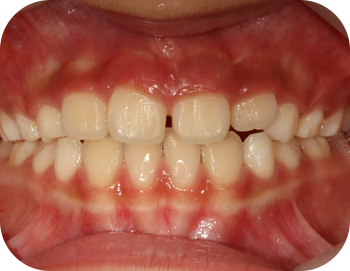

얼굴 골격의 성장에 문제가 있는지를 파악하기 위한 적절한 시기는 초등학교 입학 전인 6-7세경입니다. 이때는 유치에서 영구치로 교환되는 시기로서 부정교합 여부가 결정되는 중요한 시기이므로 이 시기를 잘 관찰하여 부정교합을 예방하는 것 또한 중요합니다. 교정의 정확한 시기는 6개월 간격으로 치과에 정기적으로 내원하여 성장 분석을 받은 후 결정하는 것이 좋습니다.